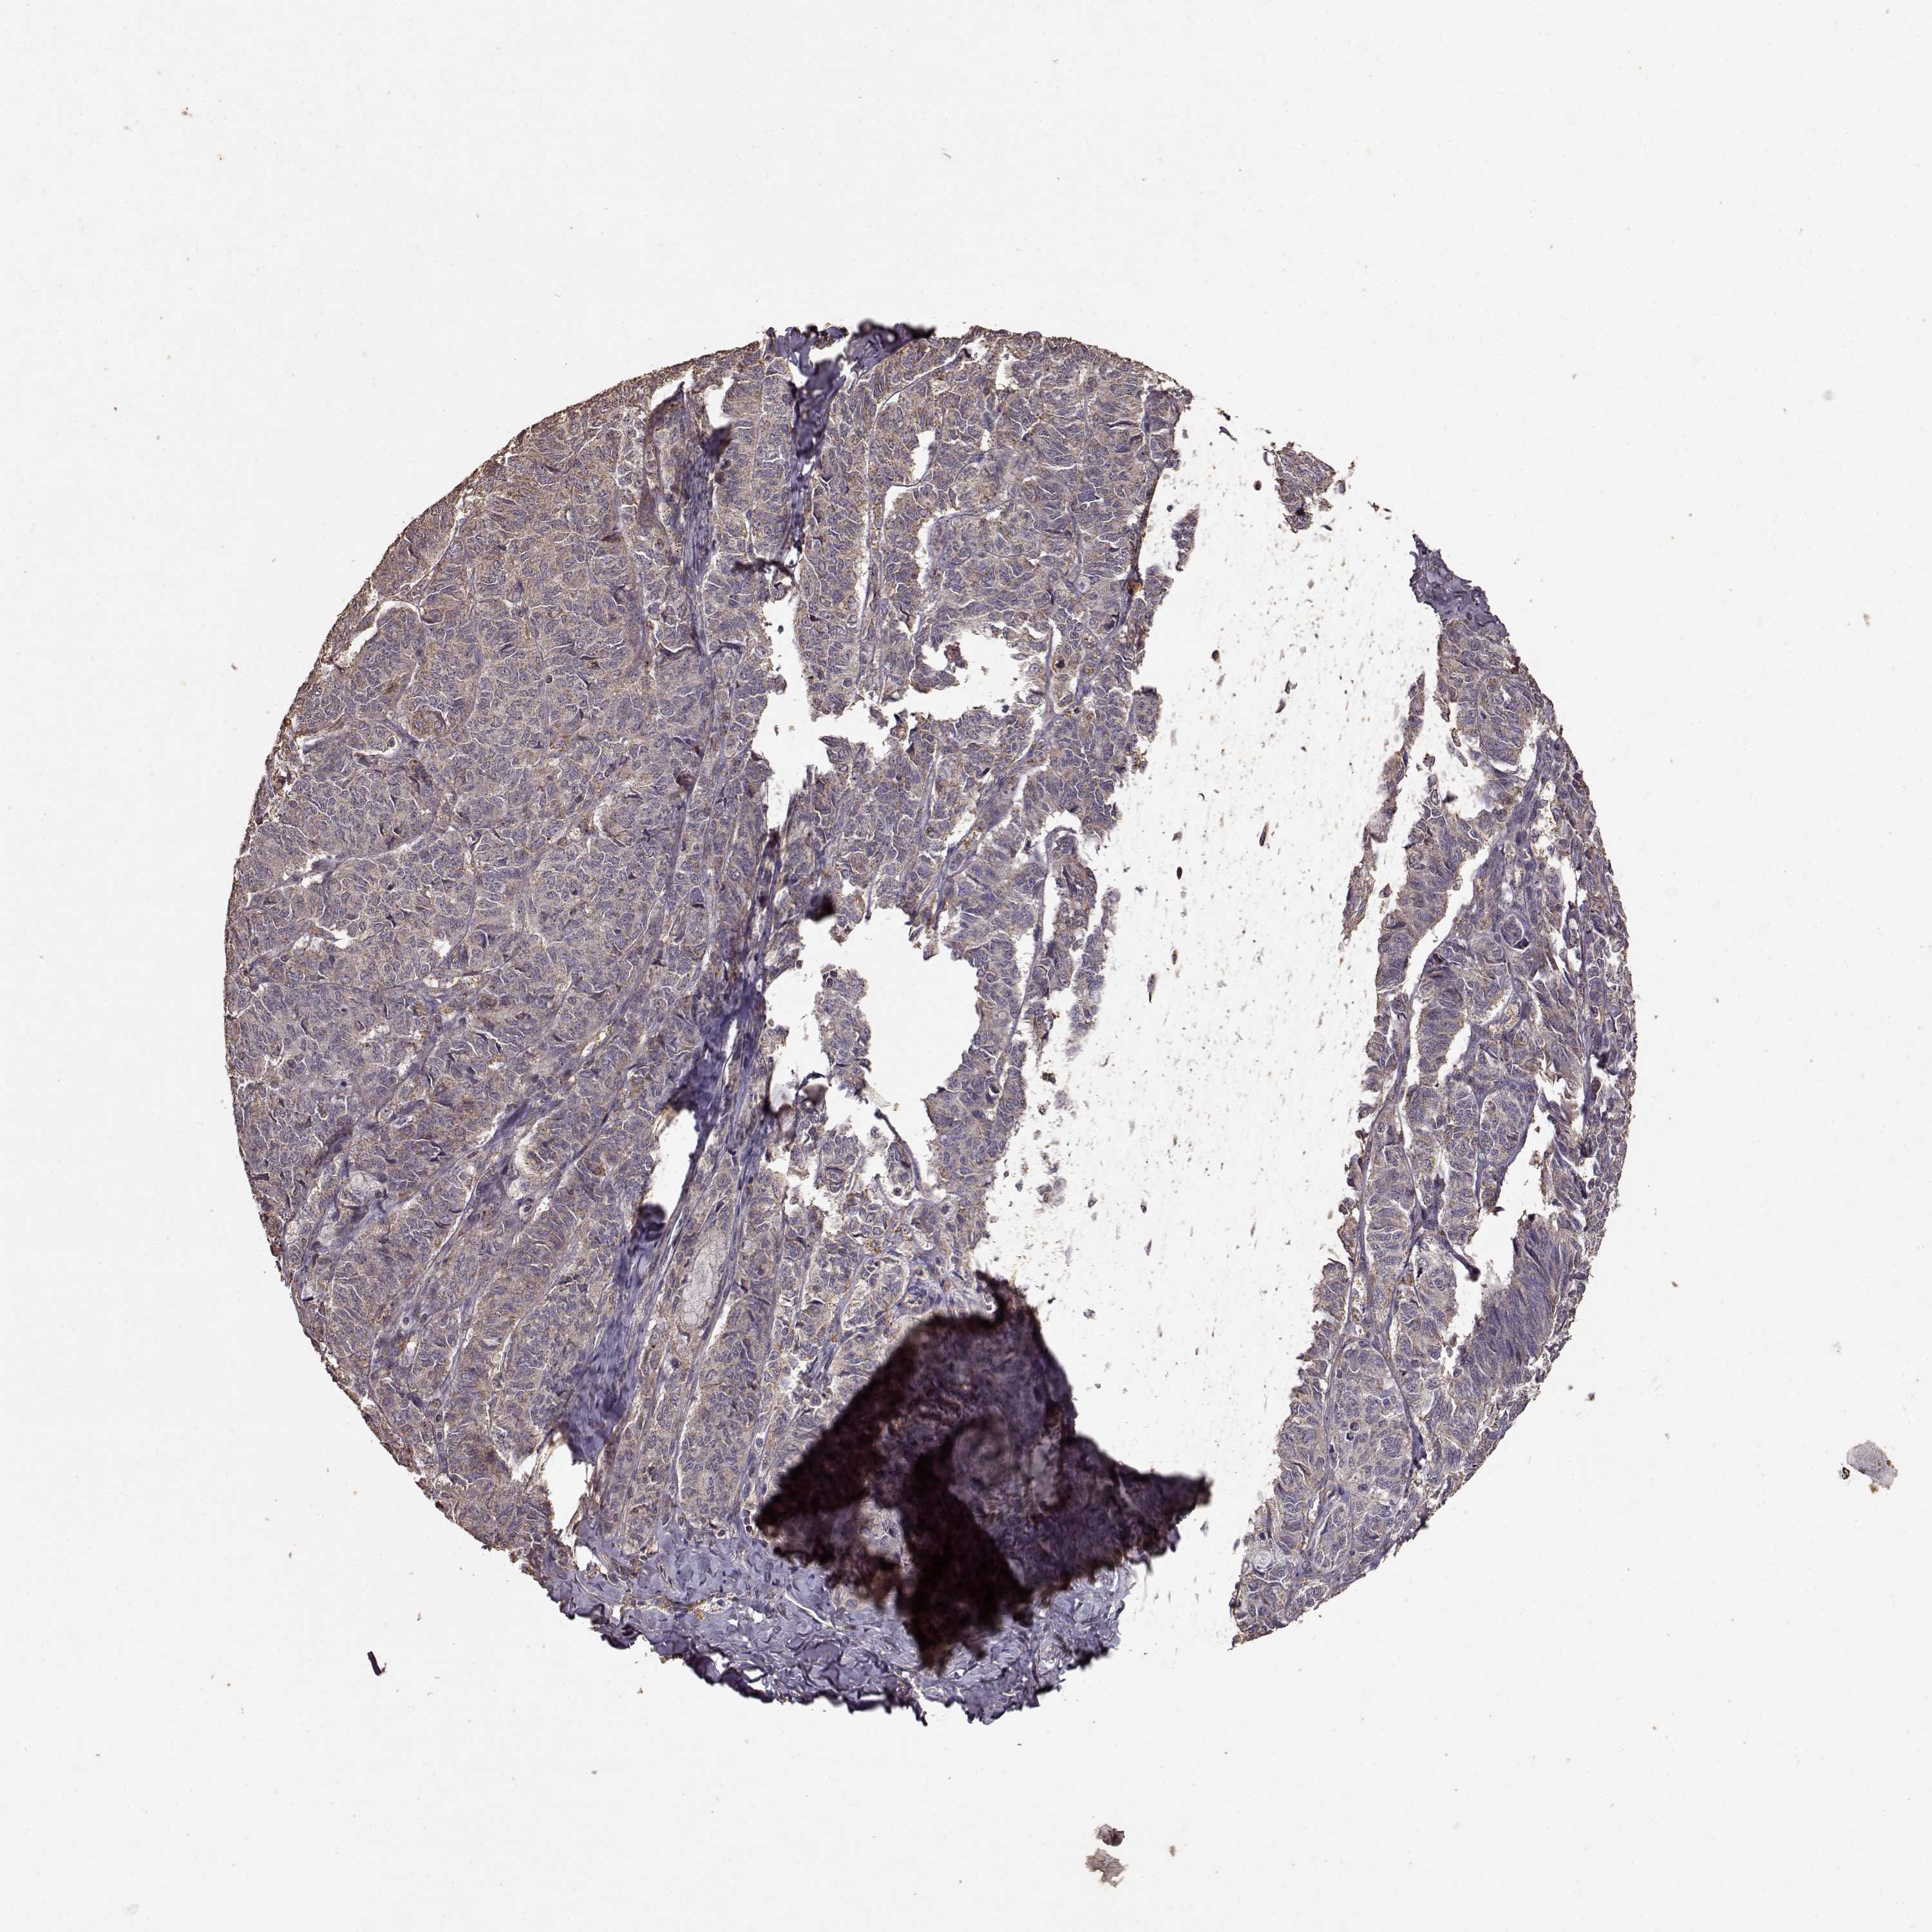

OVARIAN CANCER - Protein expressioni

A mouse-over function shows sample information and annotation data. Click on an image to view it in a full screen mode. Samples can be filtered based on level of antibody staining by selecting one or several of the following categories: high, medium, low and not detected. The assay and annotation is described here.

Note that samples used for immunohistochemistry by the Human Protein Atlas do not correspond to samples in the TCGA dataset.

Antibody stainingi

Antibody staining in the annotated cell types in the current human tissue is reported as not detected, low, medium, or high, based on conventional immunohistochemistry profiling in selected tissues. This score is based on the combination of the staining intensity and fraction of stained cells.

Each image is clickable and will lead to virtual microscopy that enables deeper exploration of all samples and also displays staining intensity scores, fraction scores and subcellular localization as well as patient and tissue information for each sample.

Antibody HPA020733

Staining

High

Medium

Low

Not detected

Intensity

Strong

Moderate

Weak

Negative

Quantity

>75%

75%-25%

<25%

None

Location

Nuclear

Cytoplasmic/membranous

Cytoplasmic/membranous,nuclear

Cystadenocarcinoma, serous, NOS

Cystadenocarcinoma, mucinous, NOS

Carcinoma, endometroid